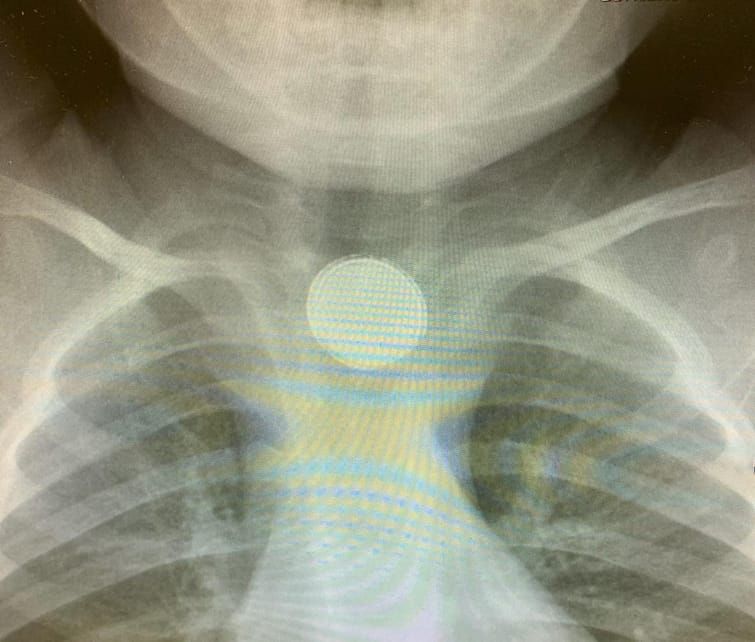

הבדיקות המקיפות כללו צילום חזה, ולהפתעת הרופאים הם הבחינו בעצם זר בצילום. לאחר בדיקה, הוברר להם כי מדובר בבטרייה (בטריית כפתור קטנה) הנמצאת לכודה בתוך הוושט של התינוק.